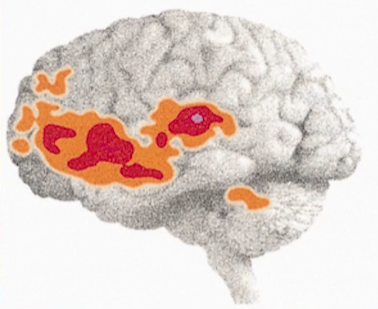

- 男女讲话的时候大脑的差异

图17-1 -

一般而言,女生沟通能力和同理心更强